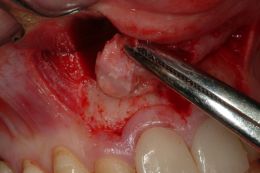

Dall'esame radiografico si evidenziano lesioni apicali a carico di tutti e due gli elementi dentari. Si sceglie per il ritrattamento ortogrado di tutti e due i denti ma per l'elemento 1.1 associato a marcato riassorbimento apicale ed apice beante si decide per una contemporanea chirurgia retrograda e chiusura in MTA.